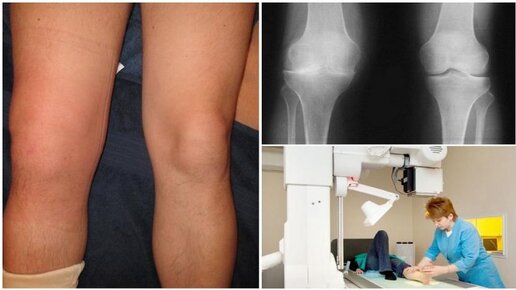

Артроз – дегенеративно-дистрофическое заболевание суставов – одна из наиболее распространенных и инвалидизирующих патологий опорно-двигательного аппарата. Дегенеративные и дистрофические процессы, то есть изменение внутренней структуры и разрушение, начинаются с хряща и постепенно распространяются на другие элементы сустава. Если такие изменения затрагивают коленный сустав, говорят о гонартрозе. Последствия артроза коленного сустава весьма серьезны: на последних стадиях пораженная нога может полностью утратить свои функции...